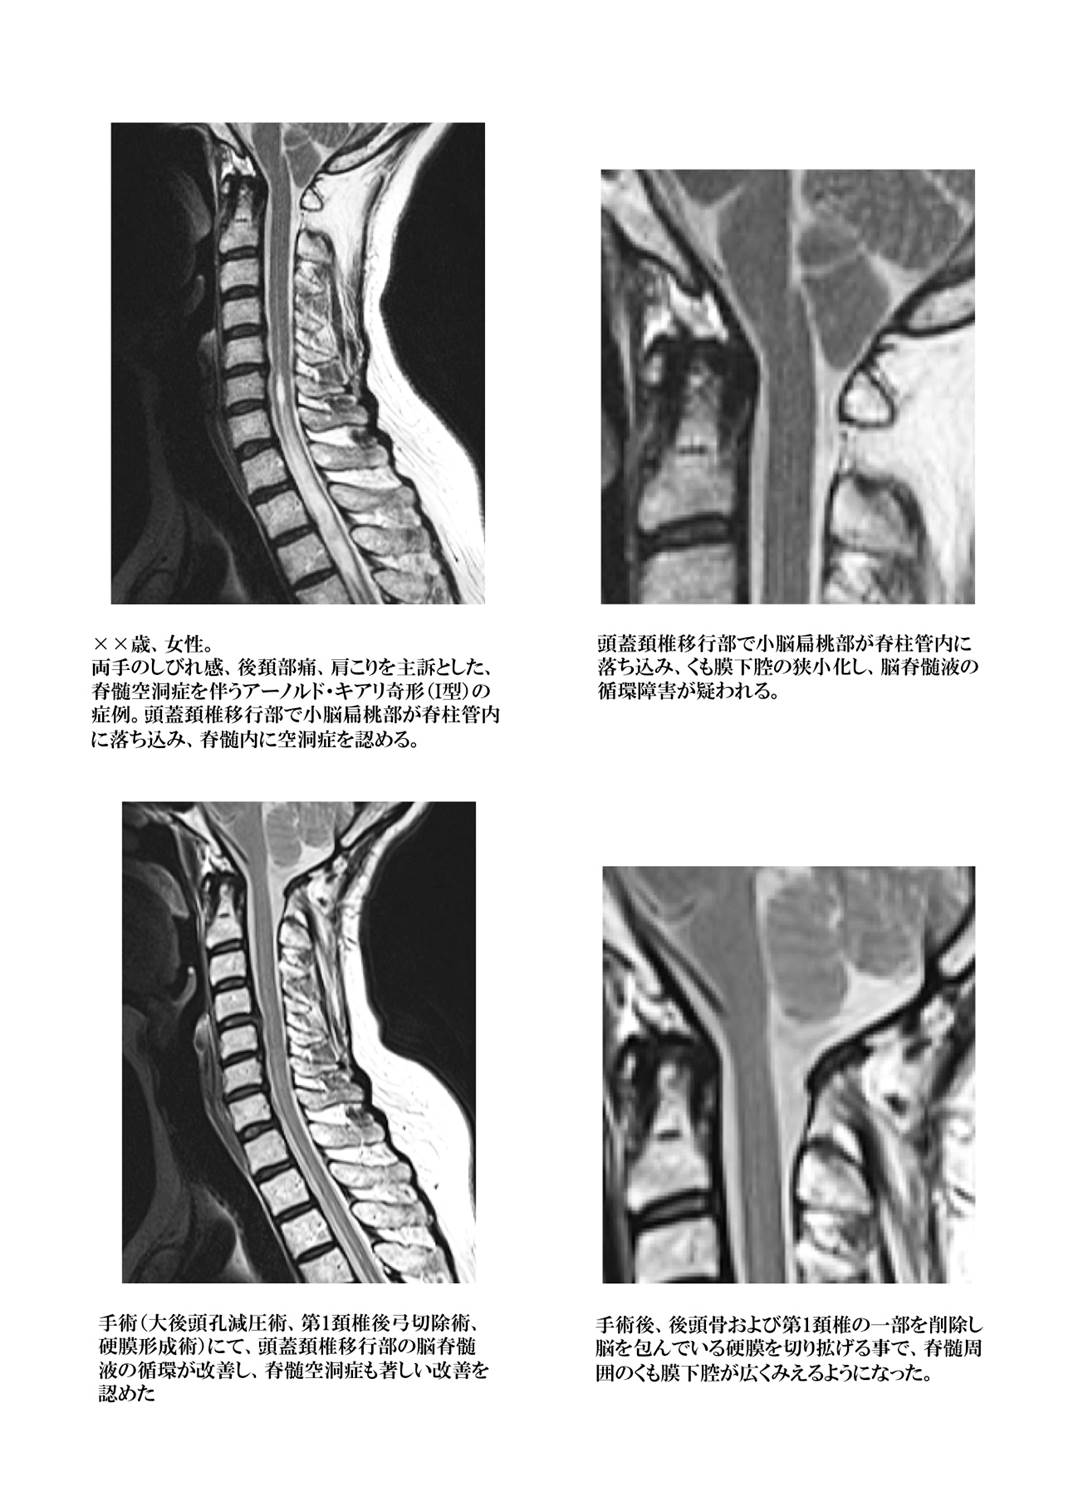

脊髄空洞症

何らかの原因により、脊髄の内部に隙間が生じて脊髄周囲の脳脊髄液が内部に貯留して脊髄自体が膨れ上がってしまう病態です。原因としては、脊髄腫瘍、外傷による脊髄損傷のほか、頭蓋頚椎移行部(頭と首の境界部)の発生異常(アーノルド・キアリ奇形)などが挙げられますが、原因がはっきりしない場合も(先天的な場合を含め)あります。

脊髄内部に脳脊髄液が貯留する事により脊髄神経組織が破壊され、上肢のしびれ感、疼痛、感覚障害、筋力低下などの症状が出現し、進行すると下肢の症状(感覚低下、筋力低下、歩行困難など)も出現する可能性があります。症状が進行してしまうと治療を行っても症状が改善しない場合が多いので、初期のうちに発見して治療する必要があります。

症状が軽度の場合には投薬にて経過を観察する場合もありますが、基本的に症状が出現した時点で根治的な治療(外科治療)が必要と考えます。原因がはっきりしている場合は原因に対する治療(脊髄腫瘍であれば腫瘍の摘出術、アーノルド・キアリ奇形が原因であれば、頭蓋頚椎移行部の減圧術)が行われます。脊髄損傷による場合や原因が不明で脊髄内の空洞が増大していく場合などにはチューブを空洞内に挿入して、空洞内と空洞外(くも膜下腔)の交通をつける手術(空洞—くも膜下腔シャント術)が行われます。

アーノルド・キアリ奇形(I型)

上記、脊髄空洞症の部分に記載があるように、頭蓋骨と頚椎の移行部分の発生異常が原因となり、脊髄空洞症を発症する事があります。頭蓋と脳・脊髄の成長のバランスが取れていない場合に、小脳、脳幹の一部が頚椎の内部に落ち込み、脊髄上端部の周囲に存在する脳脊髄液の貯留部(くも膜下腔)が狭小化して脊髄周囲が窮屈になり、脳脊髄液の循環障害を来たします。

循環できなくなった脳脊髄液が脊髄表面から少しずつ脊髄内に侵入していき、最終的に脊髄の内部に貯留していくと脊髄空洞症と呼ばれ、脳内の脳室というところの脳脊髄液の貯留量が増加すると水頭症と呼ばれる病態が合併します。この病態を4つの病型に分類して1891年に報告したオーストリアの病理学者である Hans Chiariの名前からキアリ奇形の病名がつけられました。I型からIV型まで分類されていますが、I型とII型がその大部分を占めます。治療法は外科治療以外には無く、施設によってさまざまな手術法が選択されています。

当院では後頭部のみの小さな切開で後頭骨および上位頚椎の削除に加えて脊髄を包んでいる硬膜を切開して人工硬膜を縫い合わせて拡大し、脊髄周囲の窮屈さを解決する術式(大後頭孔減圧術、硬膜形成術)を行い、良好な治療成績を得ています。